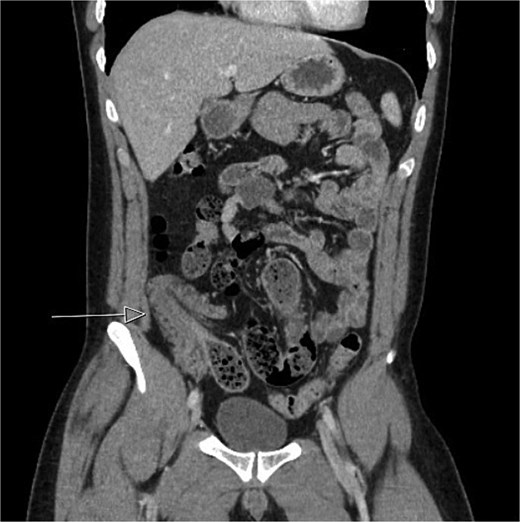

CT imaging (Figs 1 and 2) revealed an abnormal ileocolic configuration with intussusception of the distal ileal loop through the cecum. At this point, the general surgery team was consulted for immediate evaluation. Due to the history, physical exam, and findings identified on CT imaging, the patient was recommended to undergo exploratory laparotomy with intent, at minimum, to reduce the intussusception and likely perform a segmental small bowel resection to address his small bowel obstruction. Right hemicolectomy, however, was also discussed due to the patient’s family history of colon cancer to relieve the intussusception, which was causing a high-grade small bowel obstruction. During surgical exploration, the ileum was fixed within the colon, and the intussusception could not be reduced with gentle manipulation. This area of the ileum was significantly firmer than other areas, which was concerning for an ileal mass. The decision was made to resect this portion of the ileum and perform a right hemicolectomy with ileocolonic side-to-side anastomosis. The specimen was sent to pathology for further investigation. Postoperatively, the patient was hospitalized for 3 days for pain control and monitoring. He recovered in the hospital without further incident and was discharged on day 3 prior to the finalization of his pathology report.

Initial CT imaging, coronal cut, showed an abnormal ileocolic configuration with intussusception of the distal ileal loop through the cecum.